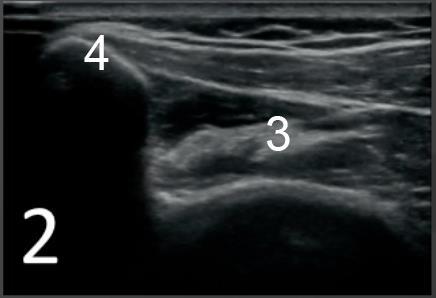

肩棘下筋横断位置2画像

2. 位置2

3. Centromusculotendonus 接合部

4. 肩甲棘